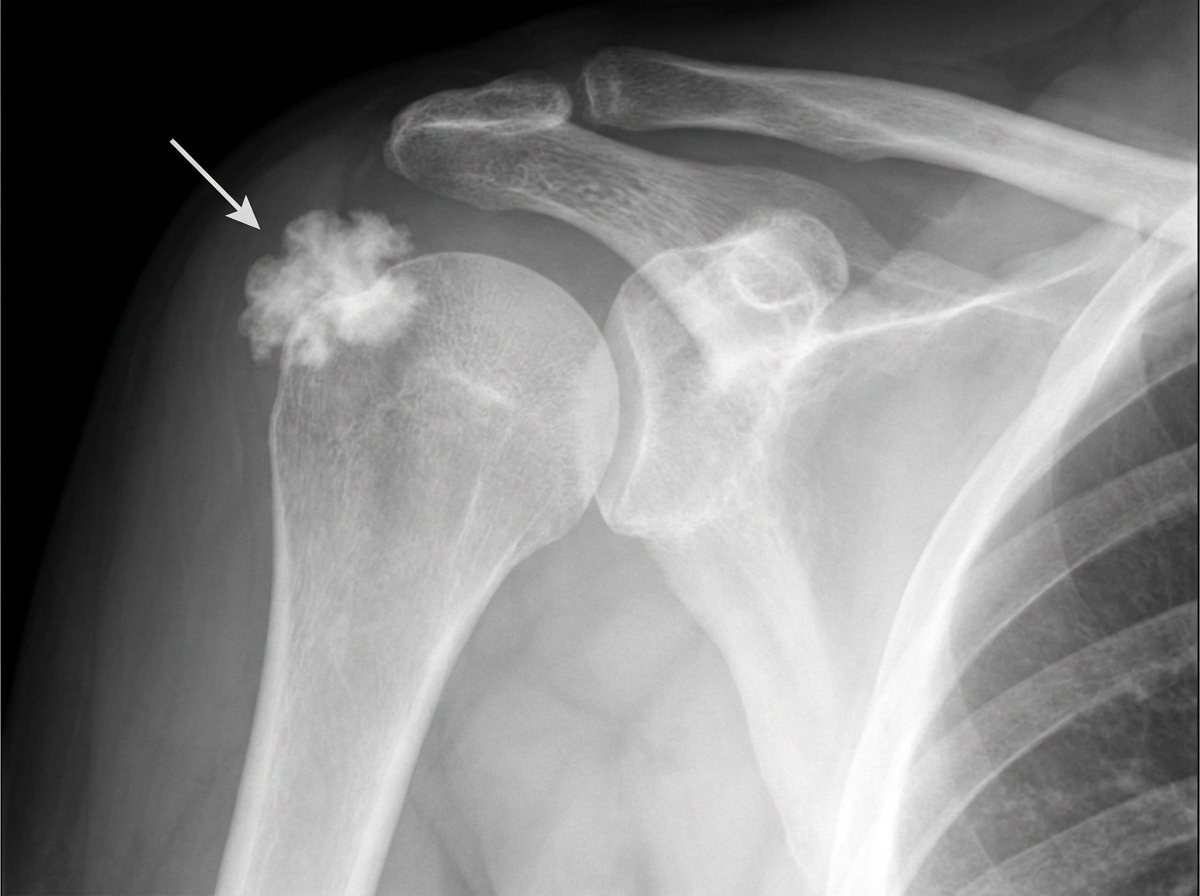

A 40-year-old male gymnast presents with right shoulder pain for 20 days. What does the arrow indicate?

Explanation: ***Supraspinatus tendon calcification*** - The arrow points to a **fluffy, cloud-like opacity** located above the **greater tuberosity**, which is characteristic of **calcific tendinitis** of the supraspinatus tendon. - This condition commonly affects **active adults** aged 30-50, particularly athletes like gymnasts, presenting with **shoulder pain** and impingement symptoms. *Calcific Biceps tendinitis* - Calcification would appear in the **bicipital groove** (intertubercular groove), not above the greater tuberosity. - **Biceps tendon** calcification is less common and would be located more **medially** on the humeral head. *Coracoacromial ligament calcification* - This would appear as calcification **superior to the humeral head**, extending toward the **coracoid process**. - The **coracoacromial arch** calcification typically presents as a **linear** rather than **fluffy** opacity. *Avulsion fracture of greater tuberosity* - Would show a **discrete bony fragment** separated from the **greater tuberosity** with clear **cortical disruption**. - Avulsion fractures appear as **well-defined bone fragments**, not the **cloud-like calcific deposits** seen in this image.